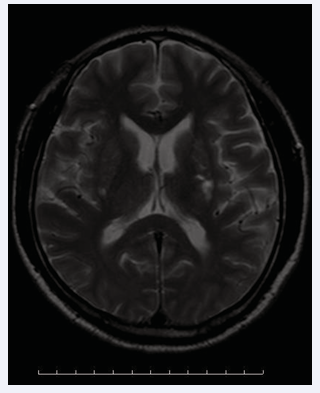

A 50-year-old man with weak left limb mobility was admitted in our hospital. Physical examination: blood pressure 140/80mmHg, clear consciousness, mixed aphasia, bilateral pupil diameter 3mm, sensitive to light reflection, muscle strength of left limb level 2, muscle strength of right limb level 5. The left Babinski sign was positive. Physical examination of the reproductive system showed no abnormalities. No skin rash or ulceration was observed in the penile anus. Head MR enhancement suggested multiple abnormal signals in the right basal ganglia/radiographic crown, considered for malignancy (Figure 1).

Figure 1 Right basal ganglia/radiographic crown occupying lesion (arrow).

Figure 1: Right basal ganglia/radiographic crown occupying lesion (arrow).